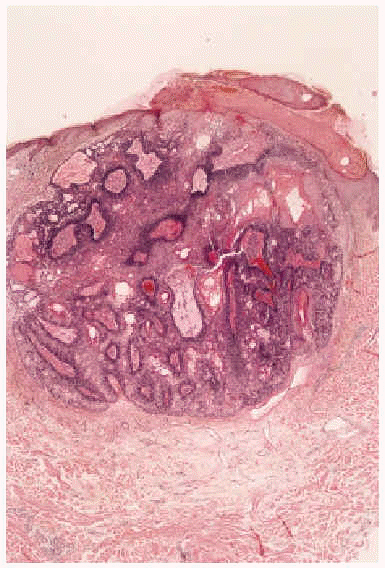

Fig. 2.--Imagen histológica del sebaceoma: nódulo polilobulado, bien delimitado en dermis superficial, con presencia de células basaloides inmaduras y nidos centrales de células sebáceas maduras sin atipia citológica (hematoxilina-eosina, 40x).

Fig. 3.--Imagen histológica del sebaceoma, apreciándose lóbulos sebáceos, de tamaño irregular, con predominio de células sebáceas maduras incompletamente diferenciadas, rodeadas de una capa de células basaloides (hematoxilina-eosina, 40x).